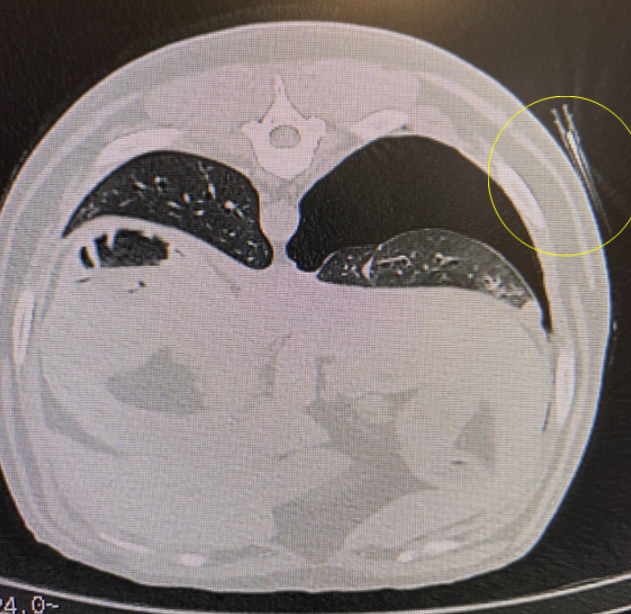

The patient was repositioned in sternal recumbency with the forelimbs extended cranially, therefore ensuring easy access to the area where the mass was located. It was possible to continue in the same examination package, so we repeated the scouts to ensure the patient was completely straight and the scanner could modulate correctly to the new patient position. The measuring tool was then employed, to measure how long the needle had to be to reach the center of the mass, and to accurately assess the required needle angle using axial, sagittal and coronal reconstructions. The distance from skin to centre of lesion was approximately 8cm (Image 7). A length of tape, marked every 1cm by small hypodermic needles, was placed over the right thorax from cranial to caudal. A scan was performed, and this allowed accurate identification of the location for biopsy needle placement (Image 8). Although this can cause artefacts, the mass could still be identified by adjusting WW and WL. The measurement tool can also be used to measure the distance from the spinous processes for more accurate location of the target area.

Image 8: Showing the needles placed on the skin to help locate position for biopsy needle placement, relative to the location of the mass.